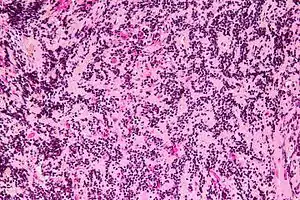

| Micrograph of a pineocytoma. HPS stain. | |

Pineocytomas are diagnosed from tissue, i.e. a brain biopsy.They consist of:

- cytologically benign cells (with nuclei of uniform size, regular nuclear membranes, and light chromatin) and,

- have the characteristic pineocytomatous/neurocytic rosettes, which is an irregular circular/flower-like arrangement of cells with a large meshwork of fibers (neuropil) at the centre.[1] Pineocytomatous/neurocytic rosettes are superficially similar to Homer Wright rosettes; however, they differ from Homer Wright rosettes as they have (1) more neuropil at centre of the rosette and, (2) the edge of neuropil meshwork irregular/undulating.